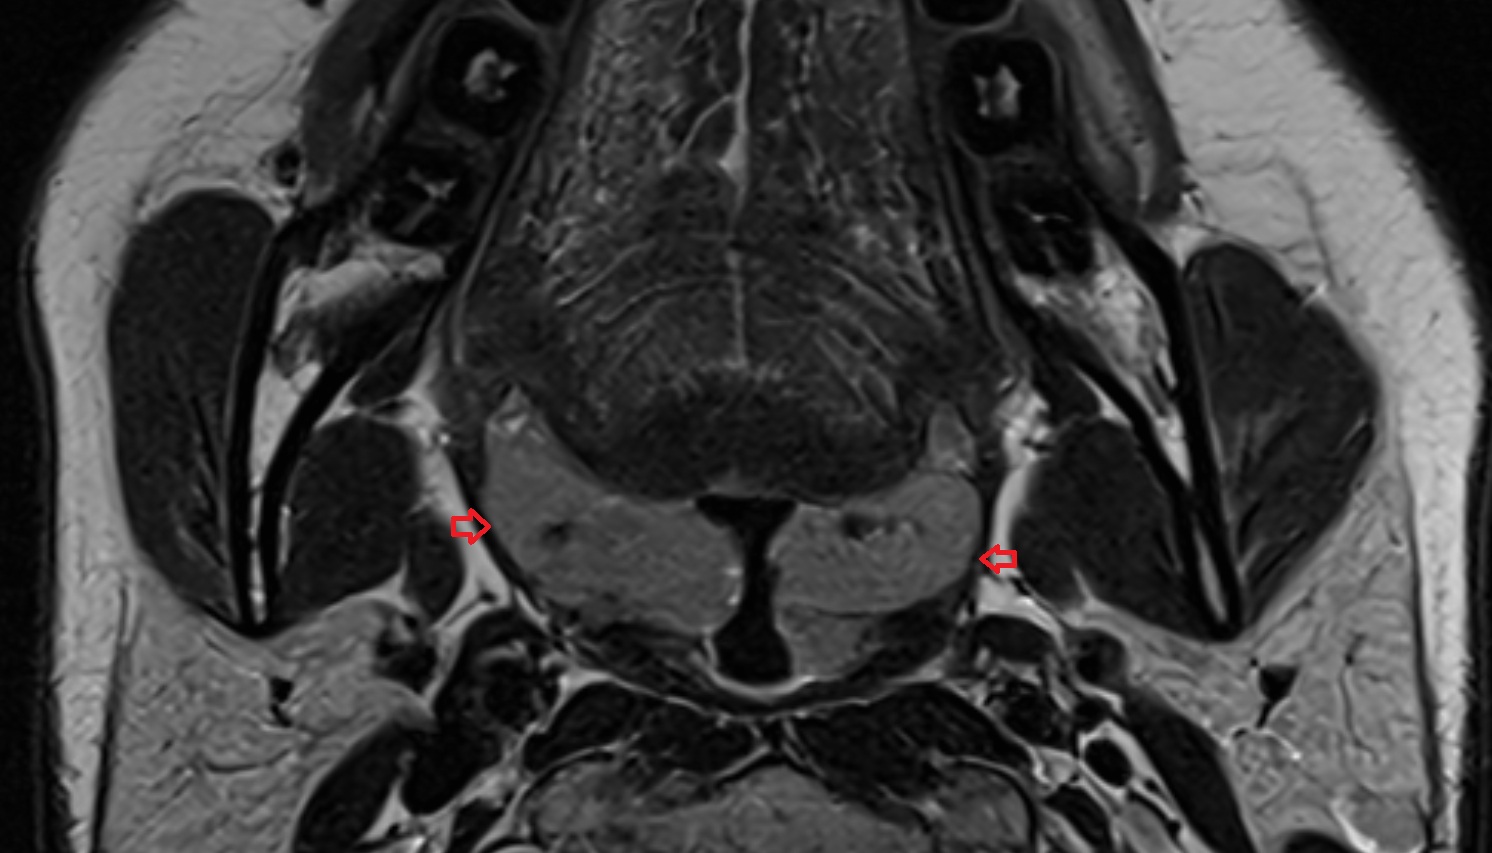

- Temporomandibular joint

- Mandibular condyle

- Mandibular fossa

- Superior head of lateral pterygoid muscle

- Inferior head of lateral pterygoid muscle

- Lateral pterygoid muscle